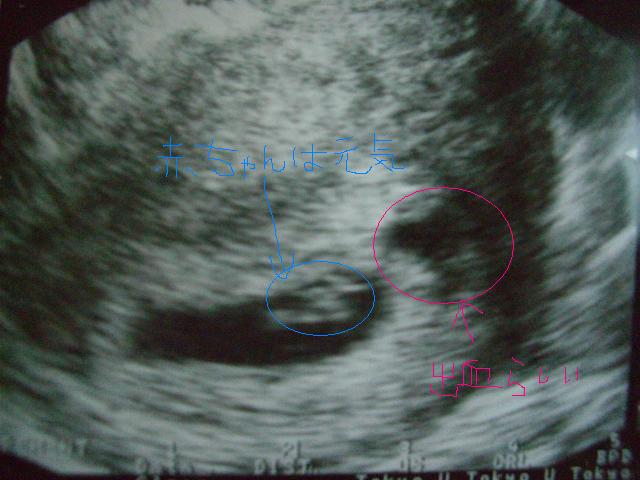

二人目

赤ちゃんは心拍も見えて元気にしてますが、近くに出血が見えるそうで

(二人目、三人目ママは抱っことかどうしても無理をしがちなので多いらしい)

問題はないと思うが念の為、しばらく安静にとのこと。